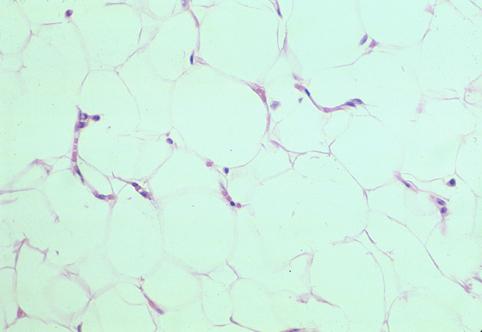

疾患(病理主体)の分類良性非上皮性腫瘍/脂肪腫

部位(臓器別)大腸/横行

検査方法ミクロ

病変の最大径(ミリ)10〜14